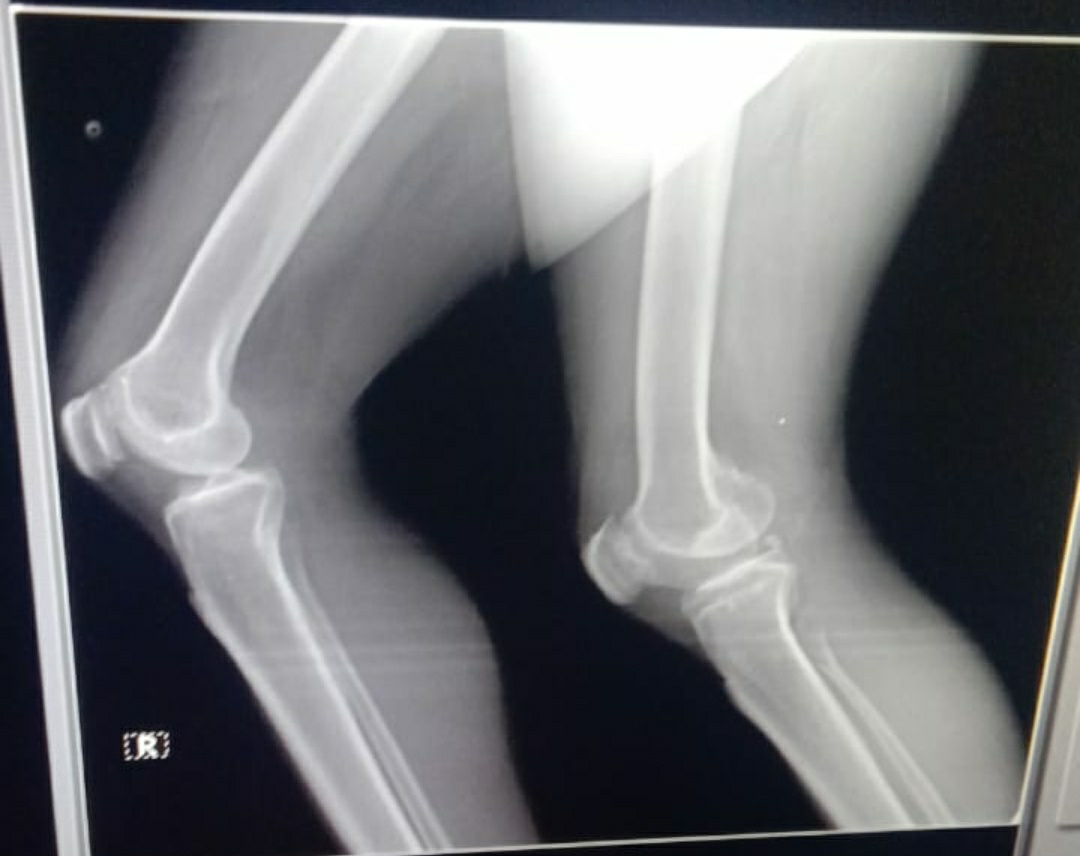

INVESTIGATIONS: